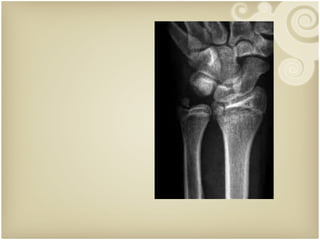

Law of Two’s  : Two views Two joints Two limbs Two occasions Two physicians Xray examination   2